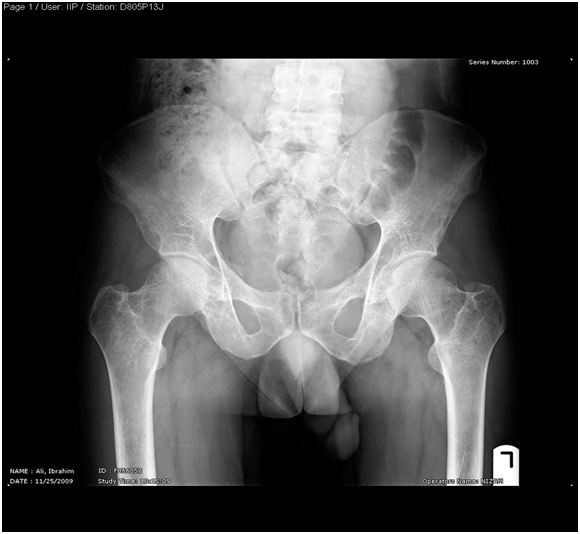

Pelvis –x-ray nov.22.2009

- R The Bones shows severe osteopenia, with appearance of Looser’s zones in the superior pubic rami, consistent with Osteomalacia…

Skeletal X-Ray: 6 months later

- Pelvis & both Femori: there is thickening of secondary bone trabeculae ,in the neck and metaphysis of both femori indicating osteopenia

- Upper Limbs & legs: normal cortical thickness but there is also thickening of secondary bone trabeculae in the distal tibia and fibula

- No Looser’s zones were detected.